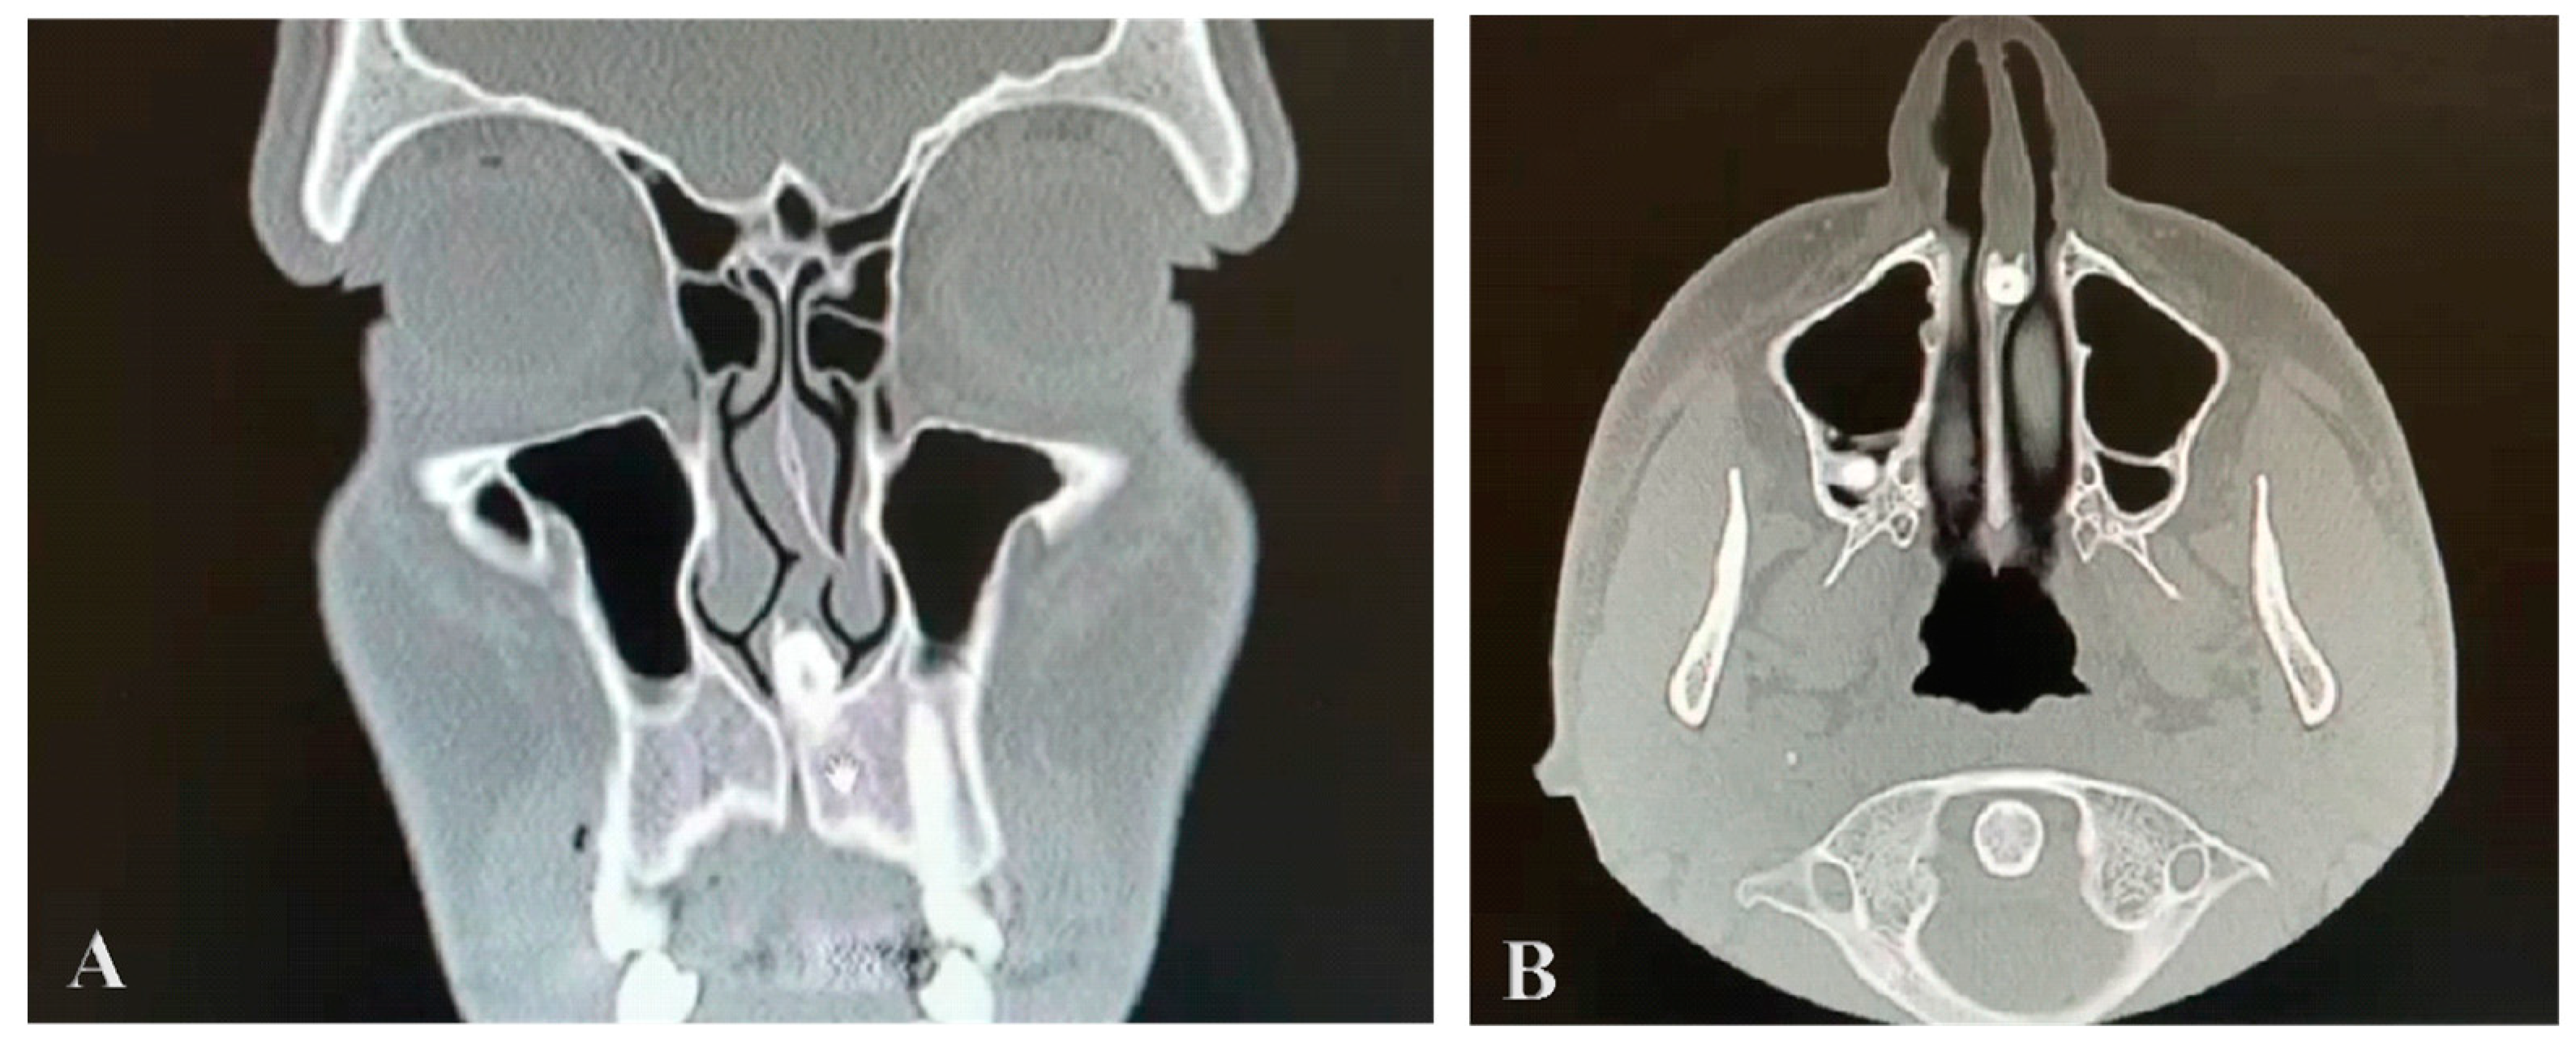

A cone-beam CT scan of the paranasal sinuses was performed, with the examination revealing nasal septum deviation, hypertrophia of both nasal turbinates, clear paranasal sinus, and the presence of a radiopaque lesion near the nasal septum with an attenuation of the mass that was the same as that of the oral teeth. It was localized in the maxillary midline area, it was set in the nasal septum and caused significant displacement of it. It was not detected during the clinical assessment because it was embedded in the nasal mucosa. A CT axial view of the intranasal mesiodens revealed its penetration into the nasal cavity, specifically located in the nasal septum. A coronal scan obtained with the bone window setting shows the crown portion of the impacted mesiodens within the base of the nasal septum (Figure 1A,B).

Figure 1. Computed tomography cut bone window coronal (A) and axial (B) views, showing the nasal tooth.